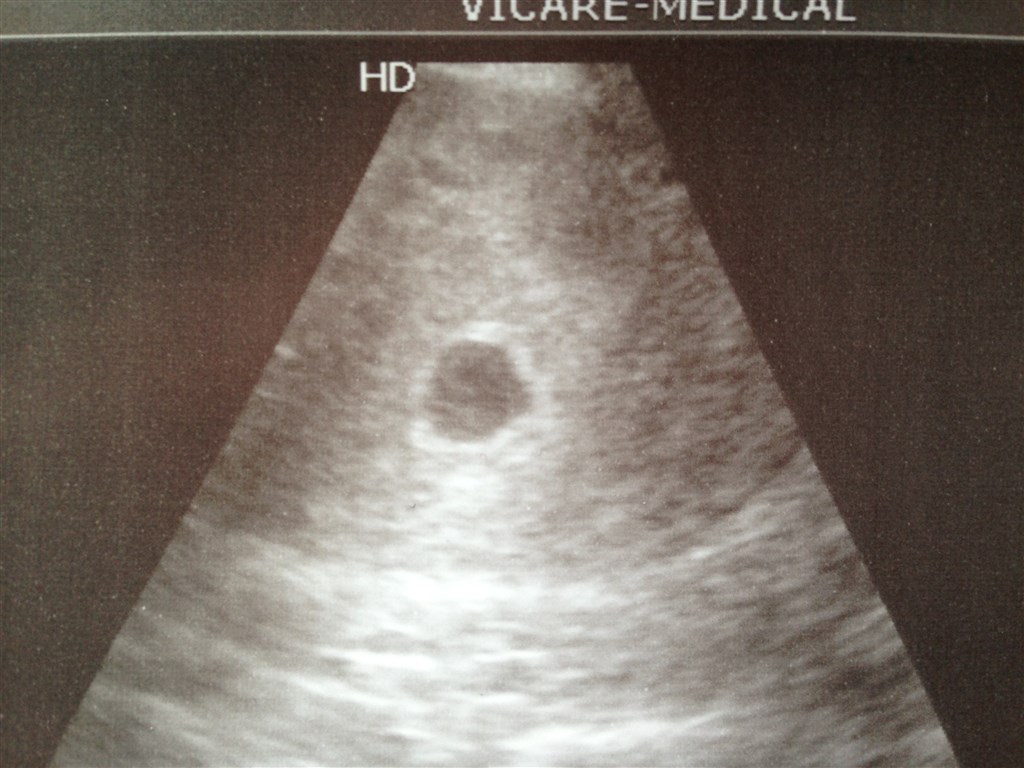

Så kom jeg hjem fra scanning, og vi venter 1 stk perfekt lille blyb, alt så helt perfekt ud

Vedhæftede fotos (klik for at se i fuld størrelse)